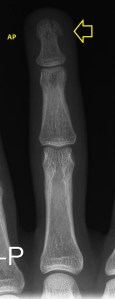

239. Fractura falange distal

En algunas ocasiones el diagnóstico de fracturas o roturas óseas no se realiza por radiografía, como normalmente se puede pensar, es más, me pasa en bastantes ocasiones que hay patologías de este tipo que veo con la ecografía y después se certifica con la radiografía.

El caso de este paciente me sirve para explicarte en este post de domingo – lunes de madrugada, no quería dejar este fin de semana sin Post. En este caso te explico como se identifica mediante ecografía una rotura ósea.

El paciente acude a la sala con una petición de su médico generalista con una petición de ecografía muscular por aumento de las partes blandas del pulpejo del tercer dedo. El paciente refiere haberse «pillado el dedo con dos mancuernas», pero no le dió importancia por ausencia de dolor y capacidad funcional plena del dedo. Cuenta que poco a poco el dedo se ha ido inflamando en la parte distal, en la yema del dedo y se ha puesto de color morado.

Solo quedaba, por si había alguna duda obtener una toma radiográfica, mira y disfruta: